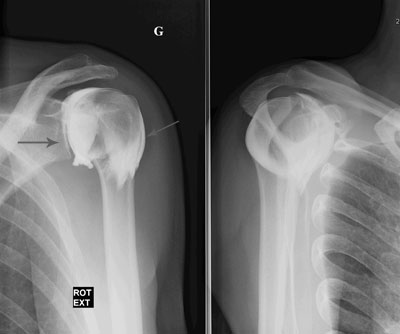

Epaule

Arthrographie de l'épaule

Capsulite rétractile arthrographie (images 1 et 2)

Arthroscanner correspondant (images 3 et 4)